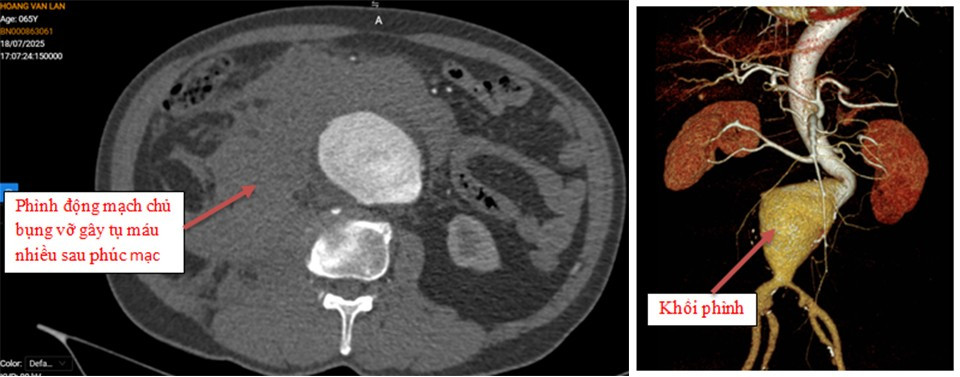

Hình ảnh phim chụp trước phẫu thuật: Phình động mạch chủ bụng vỡ gây tụ máu nhiều sau phúc mạc và hình ảnh khối phình động mạch chủ bụng trước mổ - Ảnh BVCC

Tại đây, các bác sĩ đã nhanh chóng khám lâm sàng và chỉ định chụp cắt lớp vi tính đa lát cắt (MSCT) động mạch chủ bụng. Kết quả cho thấy, hình ảnh vỡ phình động mạch chủ bụng, phình hình thoi động mạch chậu chung bên phải và túi phình động mạch chậu chung bên trái.

Người bệnh được chẩn đoán vỡ phình động mạch chủ bụng với nhận định có nguy cơ tử vong rất cao.